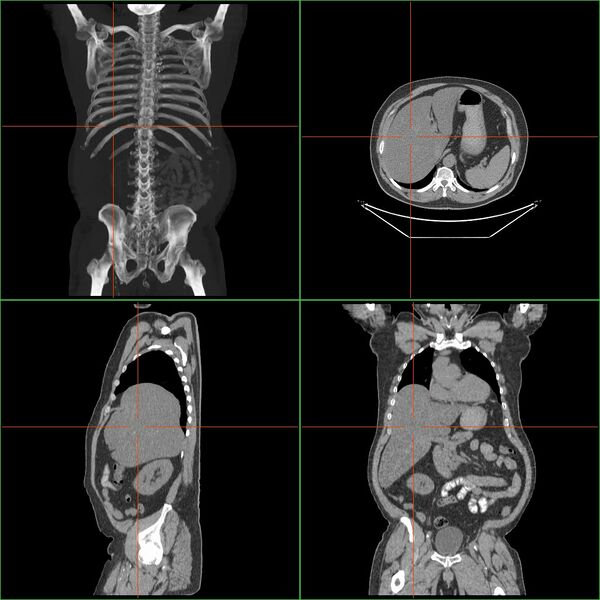

Гепатомегали́я — патологическое увеличение размеров печени.

Если размер печени по l. medioclavicularis dextra превышает 12 см или пальпируется левая доля в эпигастральной области, говорят об увеличении печени. Важно исключить опущение печени (например, при хронической обструктивной болезни лёгких или вздутии правого лёгкого) или расположение в правом верхнем квадранте других тканей (увеличенный желчный пузырь, опухоль почки или кишки). Размеры печени лучше определить посредством КТ или Ультразвуковое исследование. Важно оценить контуры и рисунок ткани органа; Увеличение тех или иных участков ткани; «каменистая» консистенция предполагает наличие опухоли; боль при пальпации говорит о воспалении (гепатит) или быстром увеличении размеров органа (недостаточность правого сердца, болезнь Бадда — Киари (Budd-Chiari syndrome), жировая инфильтрация).